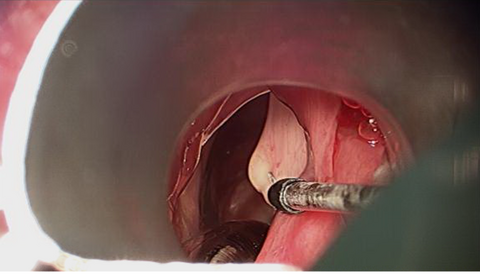

The patient elected to proceed with excision of the right vocal cord lesion with microdirect laryngoscopy under general anaesthesia (Microdirect Laryngoscopy (Suspension Microlaryngoscopy or Direct Laryngoscopy) concomitantly with endoscopic biopsy of adenoid tissue.

Intraoperative Images